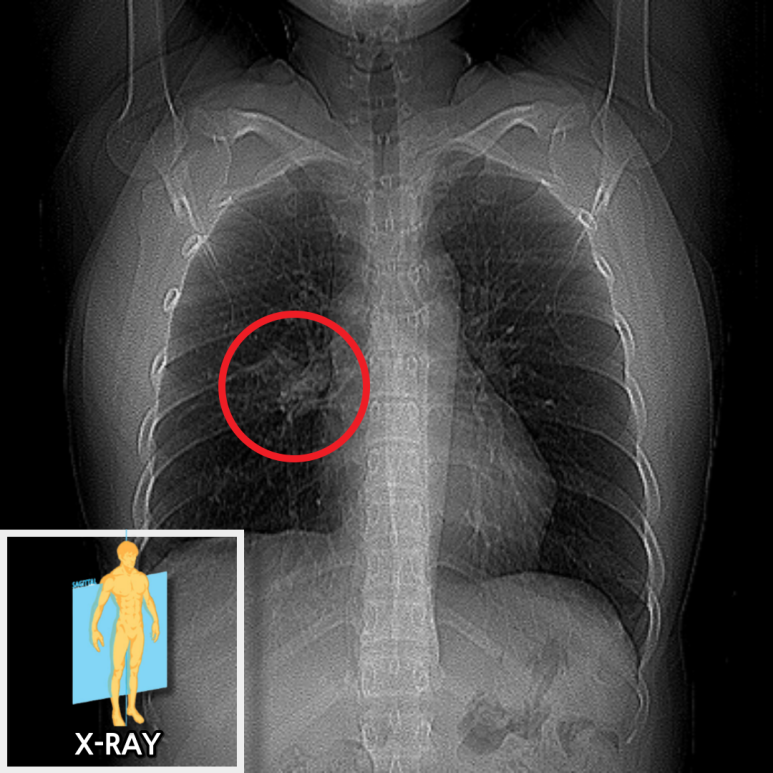

한달 이상 이어진 기침 증상과 흉부 X-ray의 비정상 소견이 있어 흉부CT로 범위와 성격을 구체화했습니다.

• X-ray 검사 결과 X-ray 검사 결과